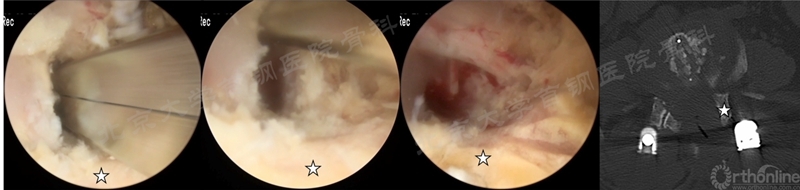

P-TLIF在UBE/BESS文献中未被直接提出,但通过文献中对手术步骤的描述笔者发现在2020年以后的BE-TLIF的文献中,多数作者不再将关节突关节完全切除,而是切除上关节突的内侧部分来完成减压和融合,这包括Dong Hwa Heo、Seok Bong Jung和中国学者Qingcheng Gao等。

我中心进行BE-TLIF时也是根据减压和植入Cage的需要来切除同侧关节突关节,部分患者术后关节突关节部分保留,这种手术方式准确来说可称为BE-PTLIF(如图11)

图11 我中心进行的一例UBE-PTLIF术中照片及术后CT资料(☆为保留的上关节突,图片来源于我中心,转发需注明出处)